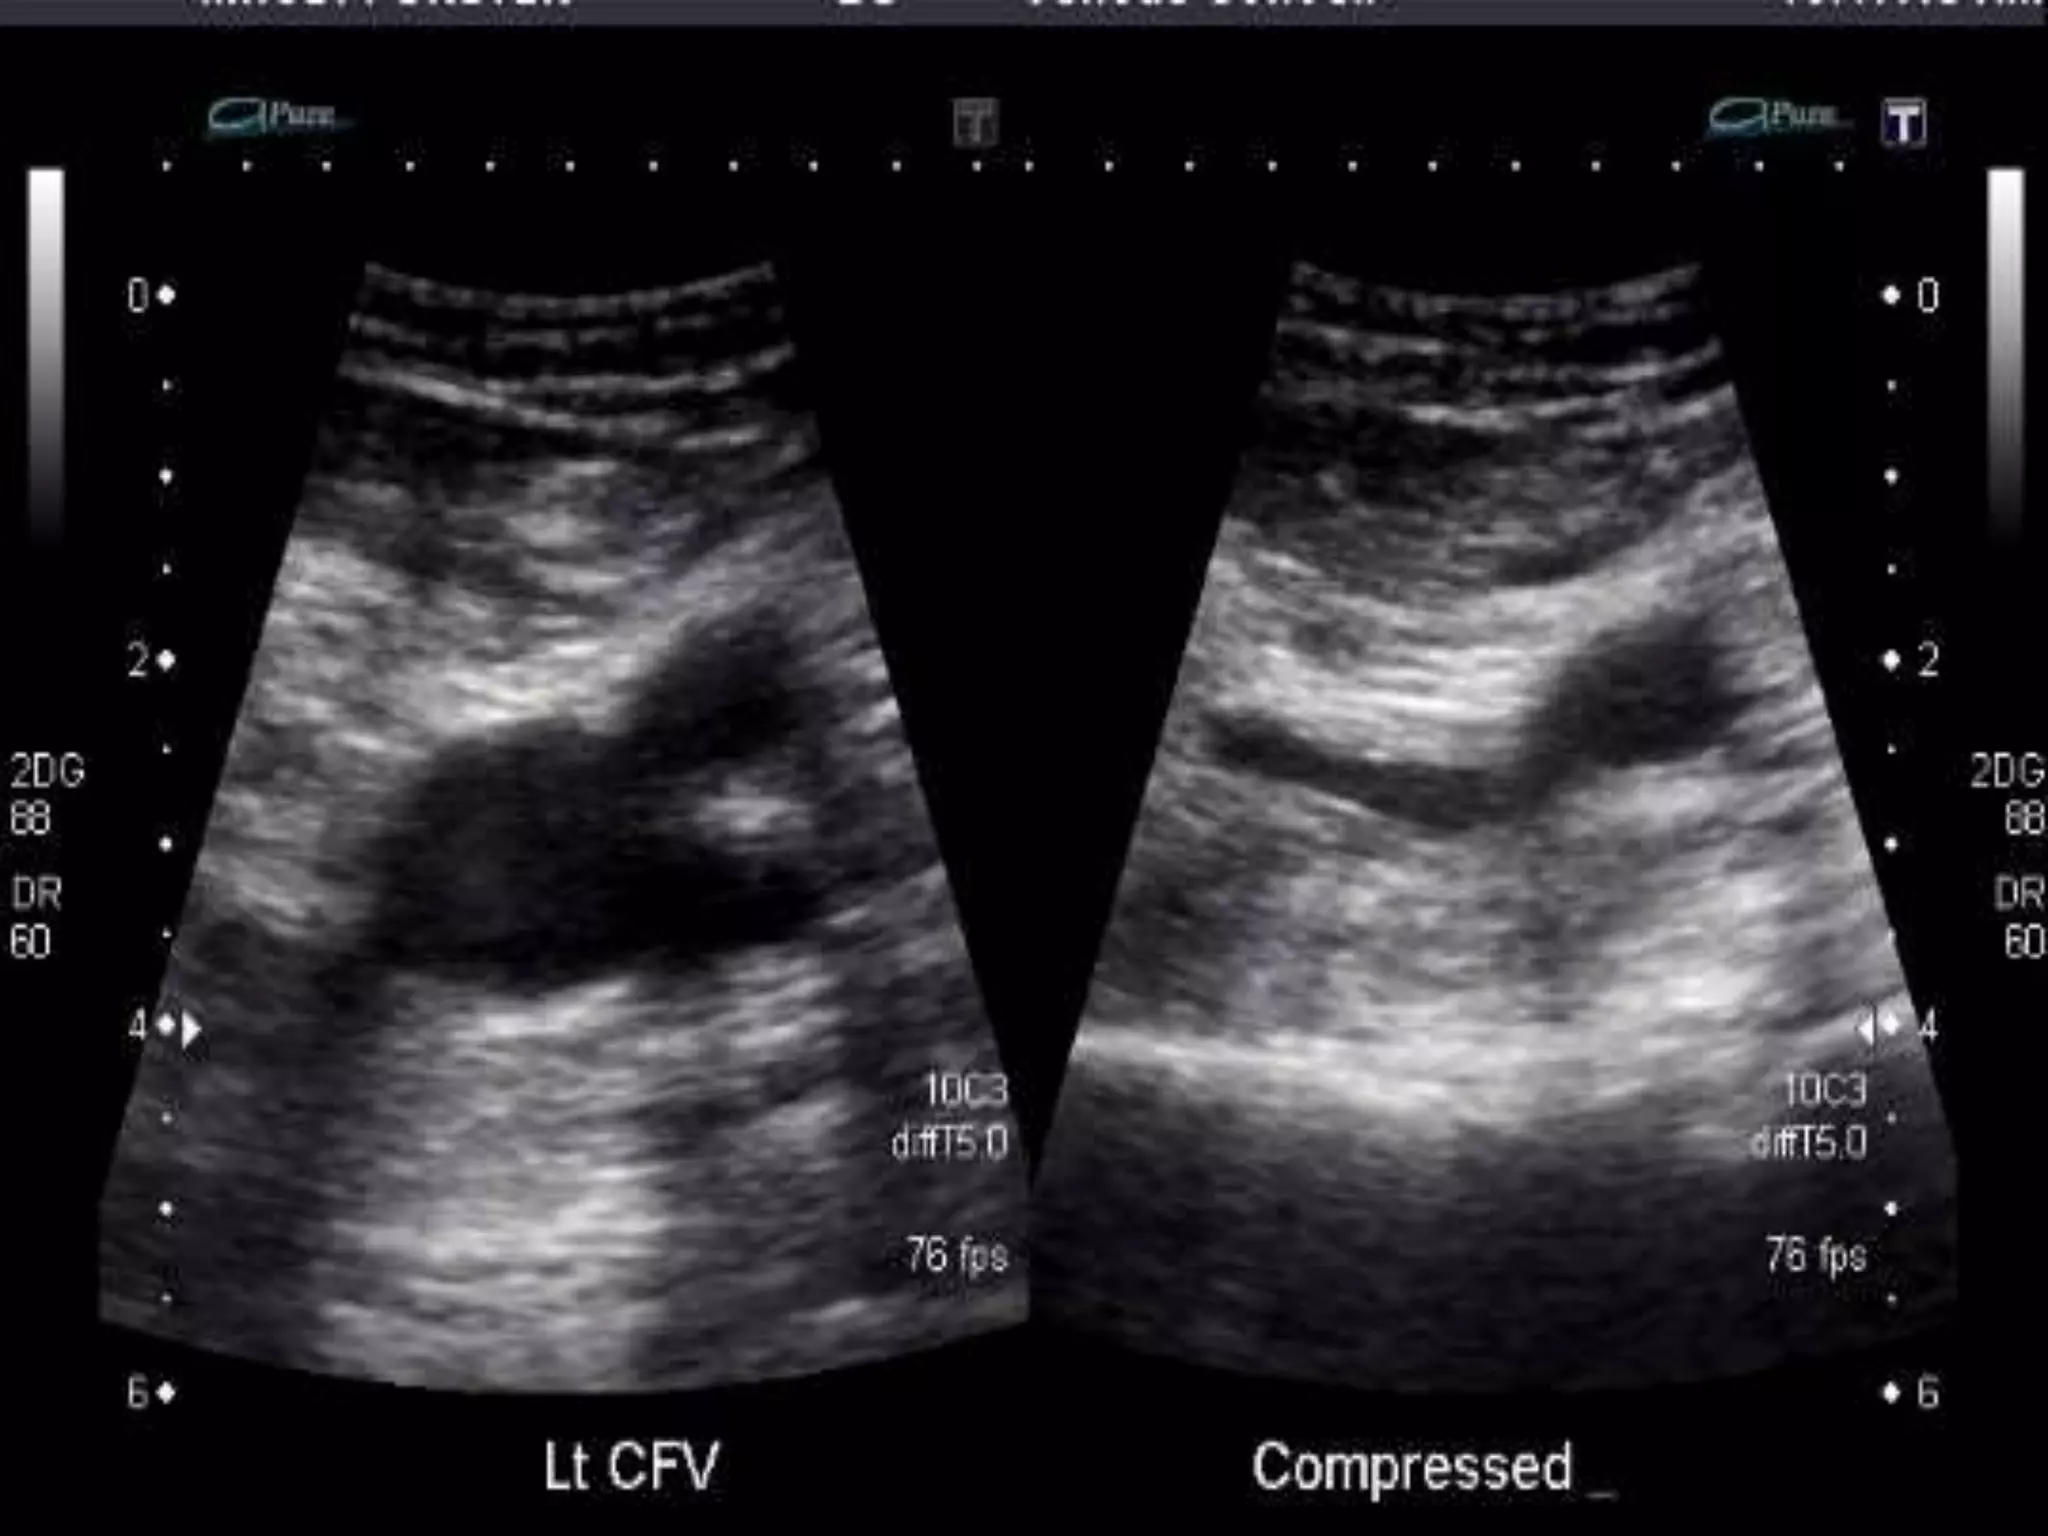

Noninvasive Imaging Modalities

• Venous ultrasonography

Ultrasonography of the deep venous system relies on loss

of vein compressibility as the primary criterion for DVT.

When a normal vein is imaged in cross-section, it readily

collapses with gentle manual pressure from the

ultrasound transducer. This creates the illusion of a

“wink.” With acute DVT, the vein loses its compressibility

because of passive distention by acute thrombus.

• The diagnosis of acute DVT is even more secure when

thrombus is directly visualized. It appears homogeneous

and has low echogenicity.

• The vein itself often appears mildly dilated, and

collateral channels may be absent. Venous flow

dynamics can be examined with Doppler imaging.

Normally, manual calf compression causes

augmentation of the Doppler flow pattern. Loss of

normal respiratory variation is caused by an

Obstructing DVT or by any obstructive process within

the pelvis.